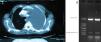

Bordetella pertussis (BP) is a small Gram-negative coccobacillus with an exclusive affinity for the mucous layers of the human respiratory tract.1 BP is an important cause of respiratory disease and it is a persistent public health problem. In 2010, a BP epidemic was detected in the city of Aydin, Turkey.2 Although pleural effusions or empyemas with BP infection are extremely rare, we present a case of non-small-cell lung carcinoma and unilateral pleural effusion with infection due to BP.A 64-year-old woman was hospitalized due to progressive dyspnea and thoracic pain. The patient had a history of non-small-cell lung cancer and she was receiving treatment. Previously, she had smoked 4–5 cigarettes per day for a period of some 10 years. Upon exploration, she showed signs of illness and emaciation, while presenting clinical anemia and signs of massive left pleural effusion on chest CT (Fig. 1). Heart rate was 85bpm, blood pressure 120/85, with no signs of heart failure. Chest radiography confirmed left unilateral effusion. Hemoglobin was 9.1g/100ml, with normochromic and normocytic blood smear. Serum levels of ferritin, vitamin B12 and folate were normal. Erythrocyte sedimentation rate was 90mm/h.Serum levels of electrolytes were normal, as were glycemia and serum calcium. The serum analyses of the liver and thyroid functions were anodyne.Pleural aspiration was performed, and 1500ml of cloudy liquid were obtained. Given the persistence of the pleural liquid collections, two days after the second aspiration a chest drain was inserted. For this pleural drainage, we used a small-caliber catheter. The protein level was 35g/l and the glucose concentration was 0.3mmol/l. No malignant cells were observed, but on PCR the presence of BP was demonstrated. The patient presented neither fever nor clinical manifestations of infection, and blood leucocyte count was normal. In addition, there were no signs of diarrhea and the stool tests, urinalysis and blood cultures were repeatedly negative. Chest computed tomography (CT) (obtained 2 weeks after drainage and treatment with erythromycin, 2mg/day) revealed enlarged mediastinal lymph nodes. The patient presents residual left pleural effusion that has not required new therapeutic drains. Several aspiration samples have remained sterile on culture.Several BP species have been associated with respiratory disease in humans. BP is more frequent and causes more diverse clinical manifestations in pediatric patients. In adolescents and adults, it is frequent for whooping cough to go unnoticed, as the only clinical manifestation may be persistent, unusual cough. Pneumonia is the most frequent complication. Cultures and polymerase chain reaction (PCR) are useful to establish the diagnosis if a sample can be obtained in an early phase of the disease.3 PCR has been widely used for whopping cough since 2001, especially in infants. The increased number of cases reported is due in large part to infection in adolescents and adults, and loss of immunity plays an important role. Although none of the patients presented immunosuppression in the conventional sense (HIV, hematologic disorders or immunosuppressive treatment), all were older patients who had underlying pulmonary problems together with other medical disorders, and all of them belonged to a population of patients that is usually vulnerable to opportunistic infections. All the patients presented signs and symptoms that were clinically compatible with respiratory syndromes caused by BP, and all responded to treatment.4In the literature, we have found no cases similar to ours, only that of a case of pleural effusion caused by B. bronchiseptica reported in a patient with AIDS.5 In the city of Aydin, in 2010 an epidemic of BP was detected,2 and we believe that our case could have originated from this epidemic. Pleural effusions or empyemas with BP infection are extremely infrequent.In our patient, there were diagnostic signs indicative of active infection. Presumably, the empyema was self-limiting. Positive PCR can be determinant in the diagnosis of limited empyema and similar latent infections. We present a very rare case of a patient with non-small-cell lung cancer and unilateral pleural effusion who presented BP infection.